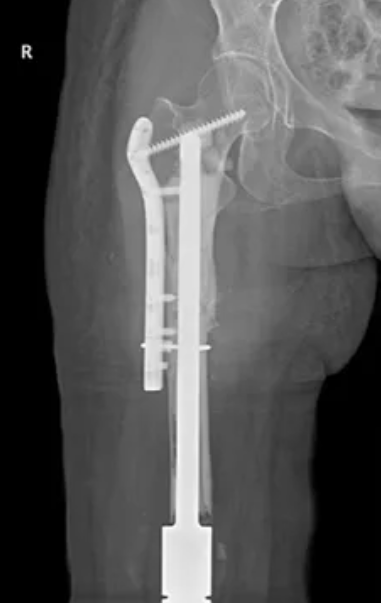

我们通过CT检查的影像数据建立三维模型,根据图像我们发现骨折处在膝关节假体髓腔杆的末端,是应力集中的部位,这个部位容易造成骨质的吸收和疲劳,导致骨折发生。如果保守治疗,发生骨折不愈合或再次骨折的风险极高。翻修手术是首选的治疗方案。手术有三大挑战:1)首先股骨上段长度较短,单靠髓内固定稳定性不够;2)其次股骨髓腔内残留的骨水泥清除比较困难;3)翻修后的肢体长度控制,在股骨长段缺损的情况下更换新假体,要精确控制双下肢长度相等。为应对挑战我们根据三维模型个性化订制了钢板和假体相结合的新假体。采用生物型髓腔杆,回植原套接在髓腔杆外的股骨段,在上下段加装钢板固定。术中使用超声骨刀对髓腔内侧参与骨水泥进行切割后清除。术后卧床支具固定四周后,在拐杖辅助下负重。

术后随访

患者术后9个月摄片复查骨折处已愈合,并且能够自主负重行走。

图示:翻修术后9个月随访